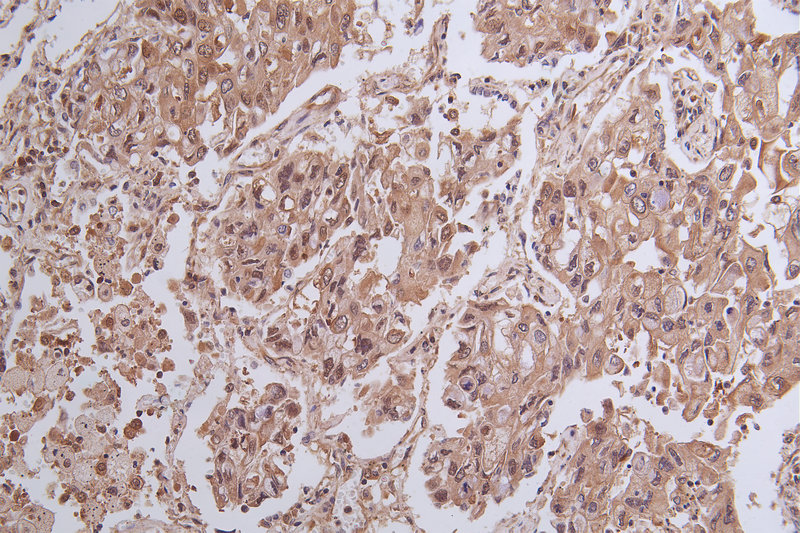

IHC image of CSB-RA824302A0HU diluted at 1:100 and staining in paraffin-embedded human endometrial cancer performed on a Leica BondTM system. After dewaxing and hydration, antigen retrieval was mediated by high pressure in a citrate buffer (pH 6.0). Section was blocked with 10% normal goat serum 30min at RT. Then primary antibody (1% BSA) was incubated at 4°C overnight. The primary is detected by a Goat anti-rabbit polymer IgG labeled by HRP and visualized using 0.05% DAB.